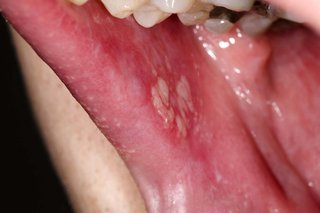

- white patches on your gums, tongue or the insides of your cheeks